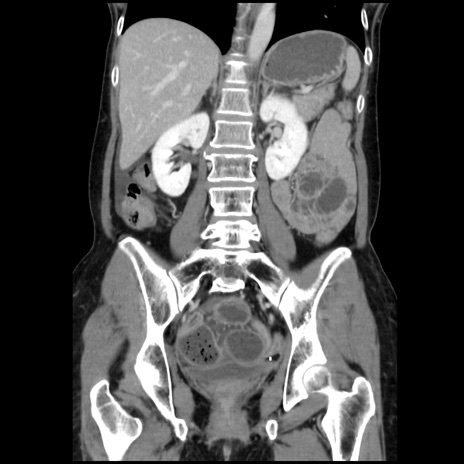

症例32(冠状断像)

【症例】40歳代 女性

【主訴】上腹部痛、嘔気・嘔吐

【現病歴】約9時間前頃から急に上腹部痛、嘔気、嘔吐が出現。改善しないため救急要請。

【既往歴】子宮頚癌(広汎子宮全摘術、放射線療法)、腸閉塞

【身体所見】腹部:平坦、軟、腸雑音亢進、上腹部を中心に腹部全体に圧痛あり。

【データ】WBC 8400、CRP 0.03